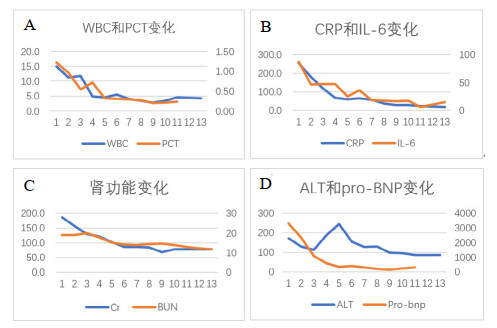

辅助检查:白细胞计数15.0×109/L,中性粒细胞百分比97.9%,淋巴细胞绝对值0.14×109/L,血小板计数344×109/L,血红蛋白94 g/L;降钙素原1.22 ng/mL,白介素6 87.5 pg/mL,C-反应蛋白254.5 mg/L;丙氨酸氨基转移酶171 U/L,天门冬氨酸氨基转移酶292 U/L,白蛋白24.7 g/L,肌酐186 μmol/L,尿素氮18.99 mmol/L,B型钠尿肽前体(pro brain natriuretic peptide, pro-BNP)3 301 pg/mL。胸部CT示两肺炎症渗出,左肺实变(图 1A)。经验性予美罗培南0.5 g每8 h一次联合莫西沙星400 mg每24 h一次抗感染治疗。行支气管镜检查留取肺泡灌洗液送痰培养和mNGS检测。在患者入院第2天,外周血mNGS检测到鹦鹉热衣原体,序列数166。改用美罗培南0.5 g每8 h一次(第1~10天)和多西环素片口服100 mg每12 h一次(第2~18天)抗感染治疗(图 2)。入院第3天的肺泡灌洗液mNGS回报鹦鹉热衣原体(序列数280)。痰培养、血培养、血隐球菌抗原、真菌G/GM试验均为阴性。入院第4天行腰椎穿刺检查,测得压力为240 mmH2O(1 cmH2O=0.098 kPa),脑脊液为无色透明,留取标本送常规、生化和mNGS。脑脊液结果提示有核细胞数为2×106/L,红细胞计数为22×106/L(参考范围 < 1×106/L),蛋白含量为34.8 mg/dL(参考范围8~43 mg/dL),葡萄糖含量为4.13 mmol/L(参考范围2.2~3.9 mmol/L)。入院第6天,脑脊液mNGS结果回报鹦鹉热衣原体(序列数4)。入院第8天复查腰椎穿刺的压力为185 mmH2O,留取标本送检。本次脑脊液常规和生化结果与第一次相仿,mNGS未检测到鹦鹉热衣原体。经过抗生素治疗(图 2),患者一般情况好转,炎症指标下降(图 3A、3B),脏器功能好转(图 3C、3D),复查胸部CT提示肺部病变吸收(图 1B),于入院第11天拔除气管插管改鼻塞吸氧,氧合99%,生命体征平稳。神志清,对答切题,语言流利,颈软。能稳准地完成指鼻试验和跟-膝-胫试验。于入院第18天出院。后随访患者恢复良好,无后遗症。住院期间头颅磁共振提示腔隙性缺血灶,未提示新发脑梗、脱髓鞘等病变(图 4)。患者出院后第5天和第44天查胸部CT见左肺渗出进一步吸收(图 1C、1D)。

| WBC为白细胞计数,PCT为降钙素原,CRP为C-反应蛋白,IL-6为白细胞介素-6,Cr为肌酐,BUN为尿素氮,ALT为丙氨酸氨基转移酶,pro-BNP为B型钠尿肽前体 图 3 住院期间重要指标变化趋势 |

鹦鹉热的治疗药物有四环素类、大环内酯类和喹诺酮类[5, 23]。该患者在当地医院接受莫西沙星为主的方案治疗,期间疾病进展,提示该抗感染方案不能有效杀灭鹦鹉热衣原体。患者入本院后,使用美罗培南联合多西环素治疗,后加用莫西沙星协同治疗。患者入院后仅出现1次发热,CRP等炎症指标下降,肌酐、转氨酶、pro-BNP等代表脏器功能的指标趋于好转。在入院第8天,患者第2次腰椎穿刺脑脊液未找到鹦鹉热衣原体,提示美罗培南、多西环素和莫西沙星可有效杀灭中枢神经系统中的鹦鹉热衣原体。后期随访患者无明显后遗症。